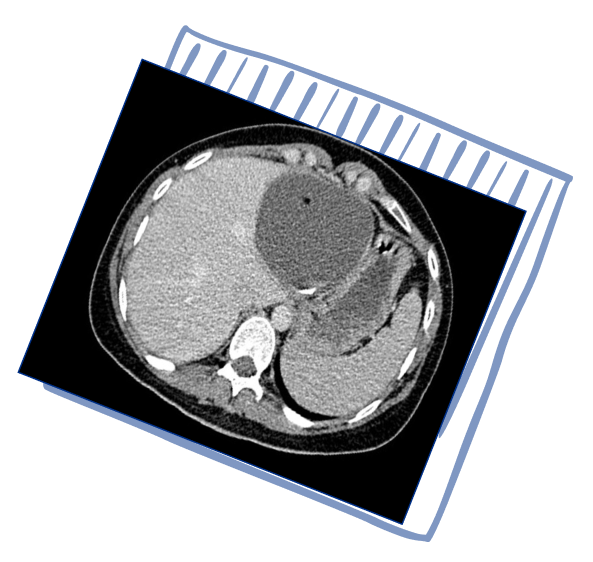

КТ брюшной полости и малого таза:

В печени выявляются гиподенсные очаги: субкапсулярно

в С7/6 печени 50х25мм, в С6 — 44х38мм, в С5 — 11х9мм,

с С7 — 11х7мм, в С3 — 15х14мм